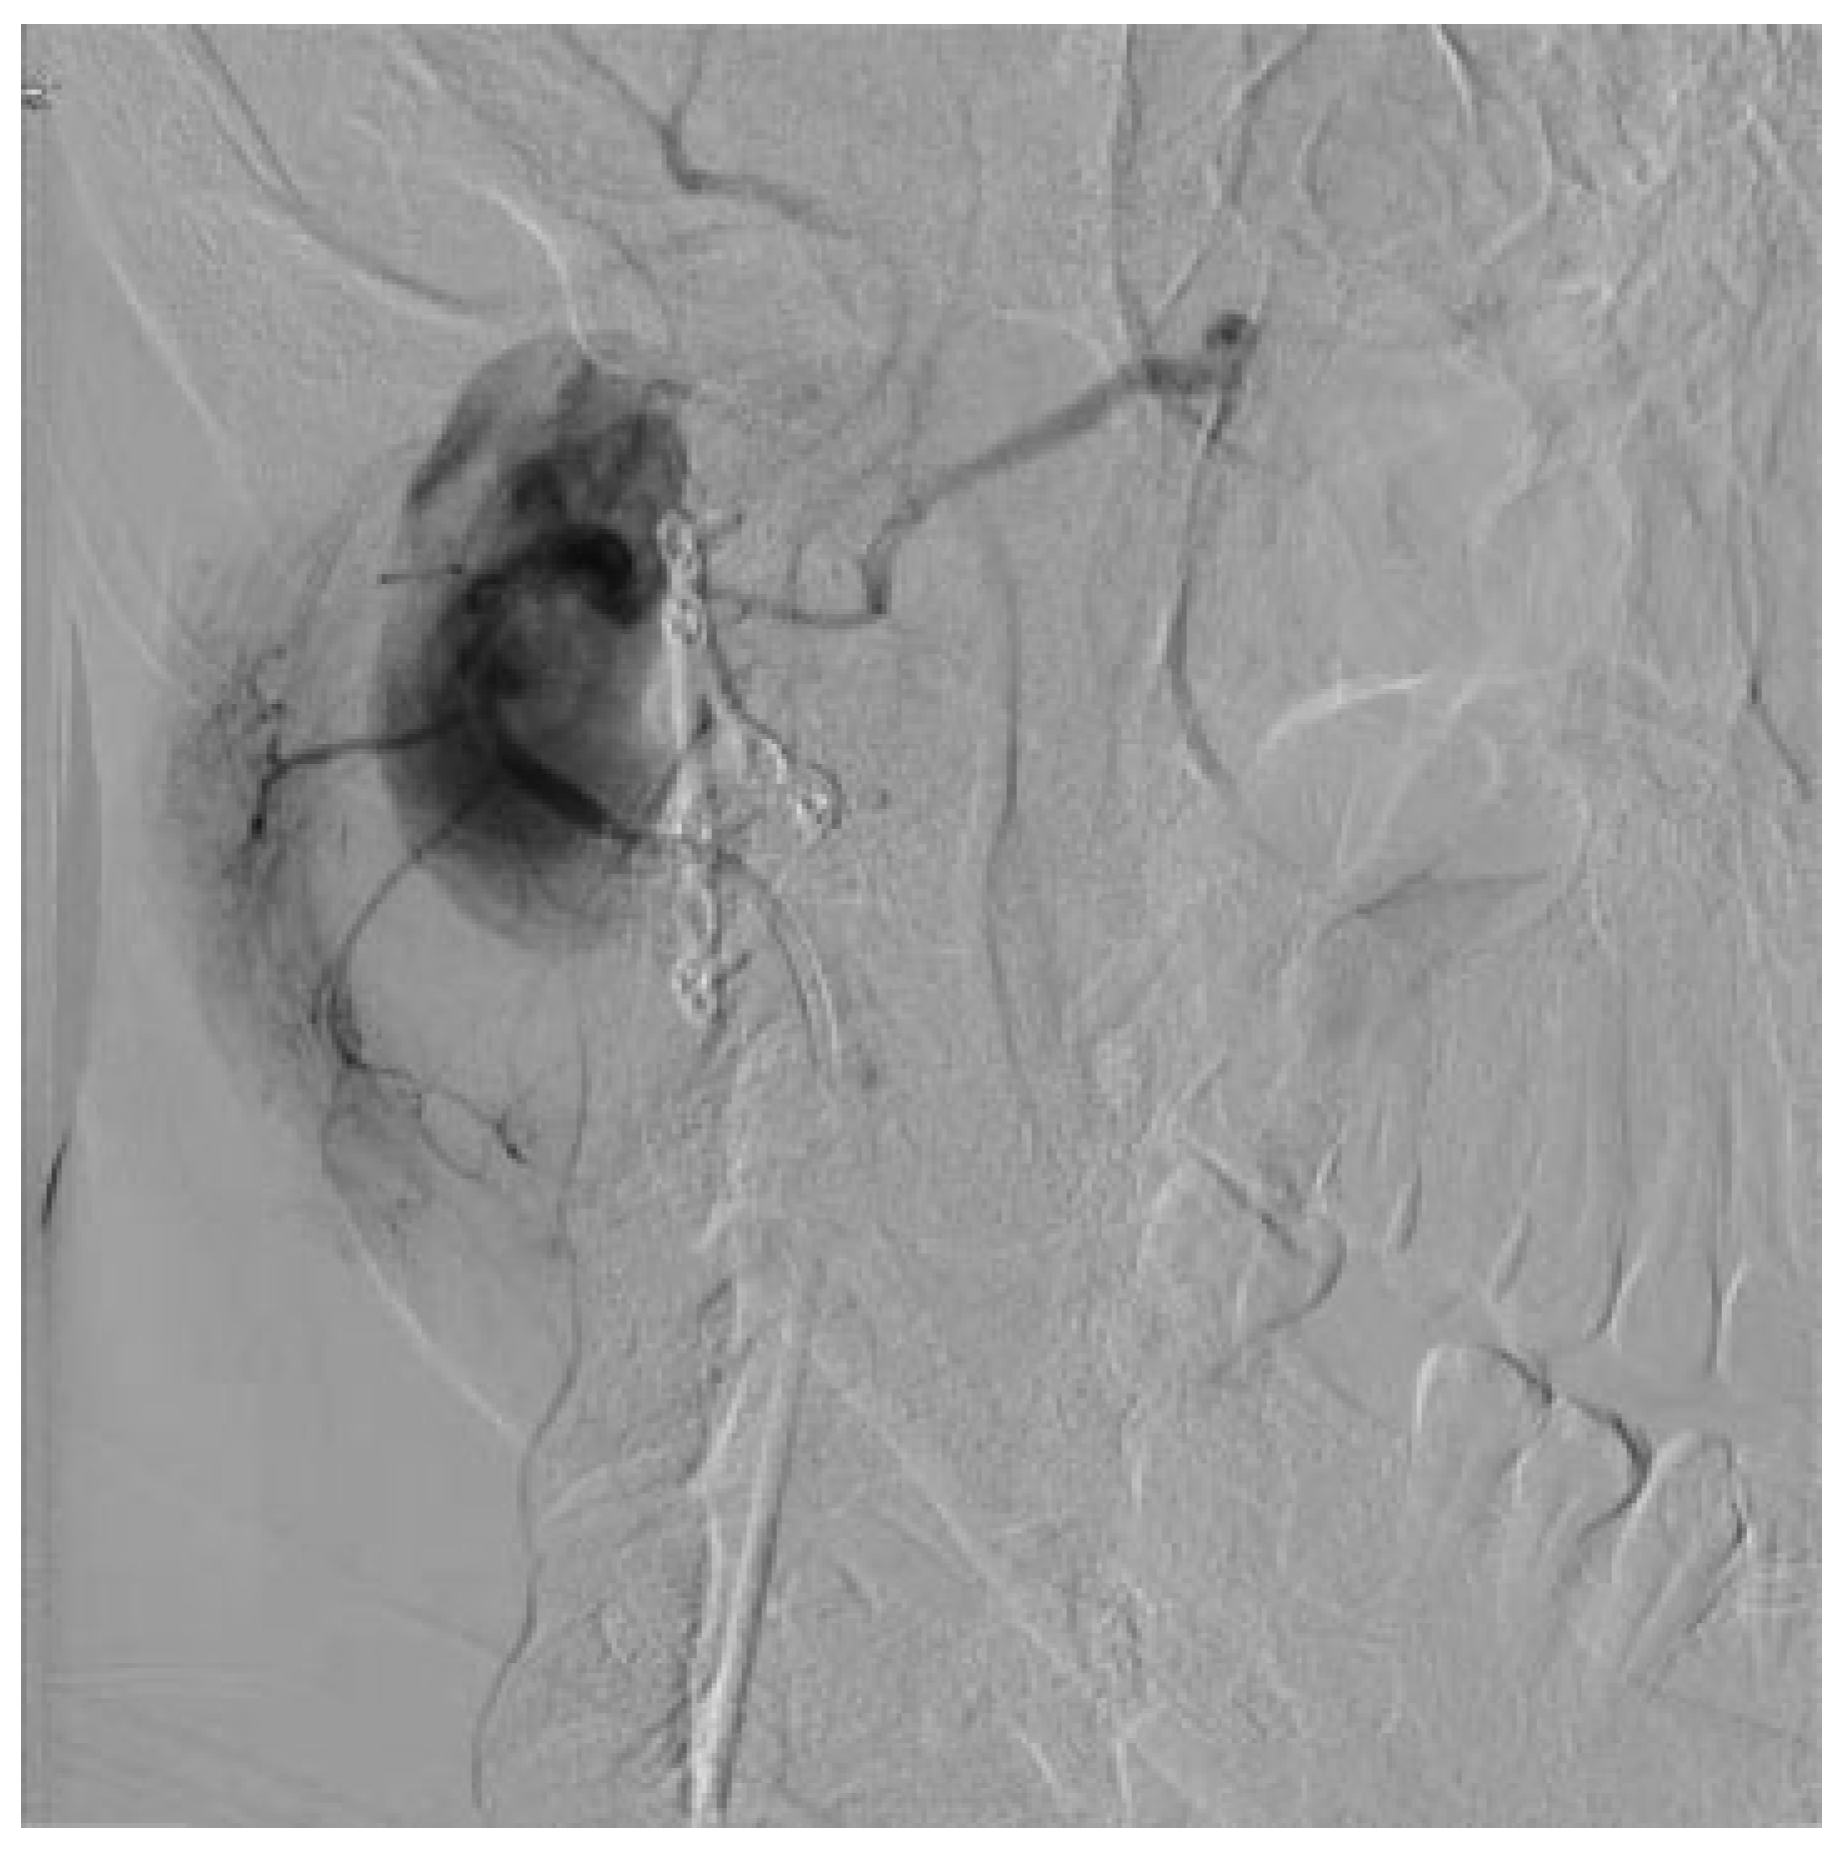

Pseudoaneurysm following Endoscopic-Assisted Repair of Subcondylar Fracture

:Presentation of Case